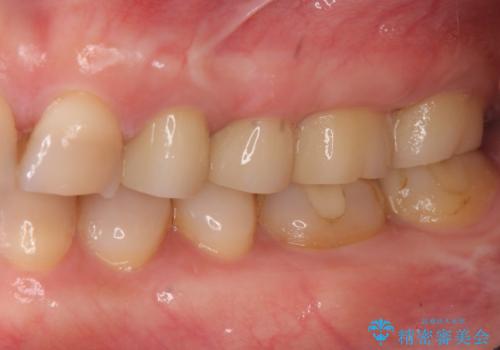

放置した虫歯 根管治療 フルジルコニアクラウン

- 虫歯治療を途中で中断し放置した歯の治療再開を希望され来院されました。

樹脂やクラウン・銀歯の老朽化がみられるため、丁寧に除去を行い根管治療を行ったのち、歯軋り・厚みの少なさを鑑みフルジルコニアクラウンによる補綴を計画します。

- 38万円(仮歯・ファイバーコア・フルジルコニアクラウン×4)費用は治療当時の料金となります